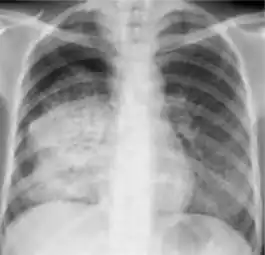

Chest x-ray of pleural thickening post-primary tuberculosis

1. Pleural thickening - Irregularity or abnormal prominence of the pleural margin, including apical capping (thickening of the pleura in the apical region). Pleural thickening can be calcified.

3. Blunting of costophrenic angle (in adults)—Loss of sharpness of one or both costophrenic angles. Blunting can be related to a small amount of fluid in the pleural space or to pleural thickening and, by itself, is a non-specific finding (except in children, when even minor blunting may suggest active TB). In contrast a large pleural effusion, or the presence of a significant amount of fluid in the pleural space, may be a sign of active TB at any age.